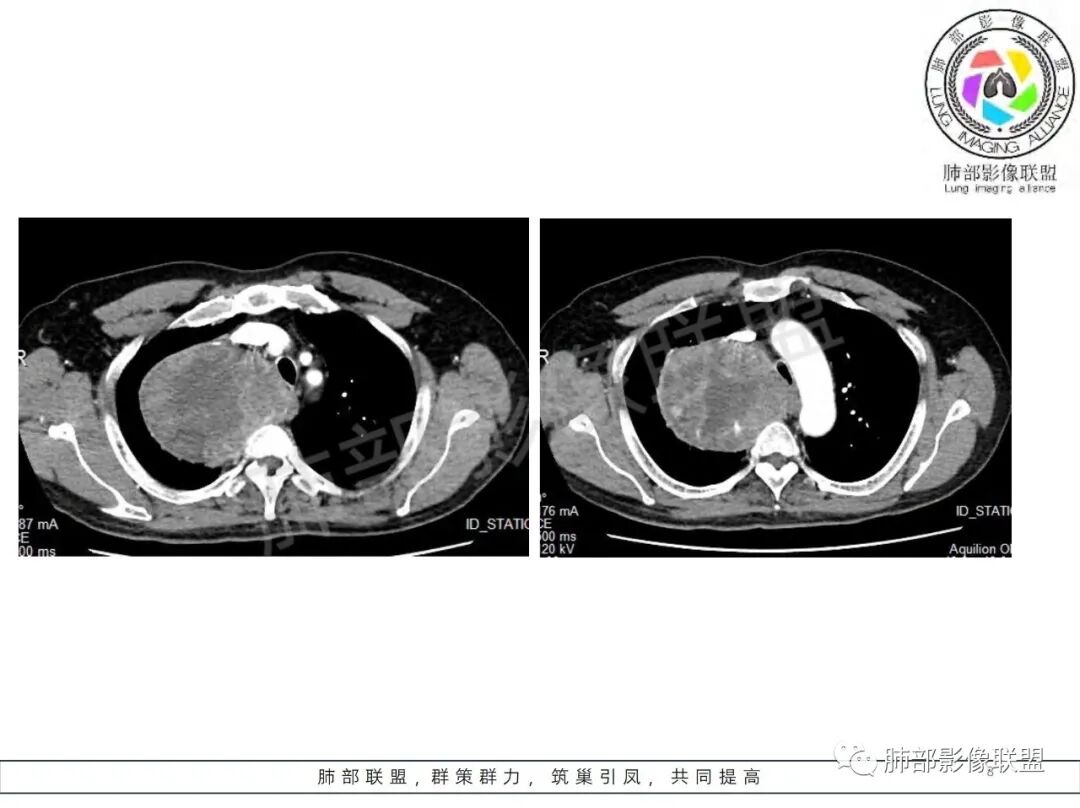

晨读病例,62岁男性,间断咳嗽四个月,影像表现右侧胸腔内见巨大肿块影,边界清晰,其内密度不均,增强扫描病灶呈不均匀性强化,病灶内见坏死及强化的小血管影,考虑恶性病变,肉瘤类病变,纤维肉瘤,滑膜肉瘤,癌肉瘤,恶性纤维组织细胞瘤。

男,62,间断咳嗽4月。胸部CT:右侧胸腔大肿块,向内压气管,向前压上腔Ⅴ,向外挤压右上肺,右上肺体积缩小,瘤肺界面清楚,交界处可见压缩带,胸膜尾可见,平扫密度不均匀,增强可见大片低密度区,AB区?考虑肺外来源,N源性肿瘤(鞘瘤)?SFT?鉴别胸腺肿瘤,肺肉瘤等。

男,69岁,间断咳嗽4个月,右上肺体积缩小,可见巨大软组织占位,胸膜掀起,考虑来源于肺外,平扫密度不均匀,增强扫描明显不均匀强化,内部可见粗大血管及坏死区,周围组织受压移位。局部与食管分界不清,穿刺提示短梭形细胞,来源于间叶组织可能,综合考虑为神经鞘瘤>SFT

边界清楚、光滑,D字征,与肺血管、支气管关系不密切,胸膜被掀起都提示肺外来源

上腔静脉受压前移

孤立性纤维性肿瘤(SFT)

是一种少见的梭形细胞间叶组织源性肿瘤,大多数为良性和中间性,少数为恶性,可发生于全身各个组织,最常发生于胸膜,其他有腹膜腔、腹膜后等。

好发于肺胸壁交界区或纵隔交界区,病灶部位对病灶性质判断有较大价值。多单发,有包膜,边界清。

密度:与肿瘤细胞疏松或密集、胶原纤维含量、出血、坏死、囊变及黏液变性等有关。镜下由梭形细胞组成、细胞间由胶原纤维沉积,CT平扫肿瘤实性部分为等、稍低密度,胶原纤维易发生黏液变性或囊变,呈多发灶性或不规则星芒状低密度区,较少出现钙化。一般肿瘤小,密度多均匀,肿瘤大,多发生坏死、囊变,密度多不均匀,。

强化方式:多均匀或不均匀明显强化,增强肿瘤内可见迂曲血管影(蛇纹血管等),肿瘤较大可见“地图样”强化。